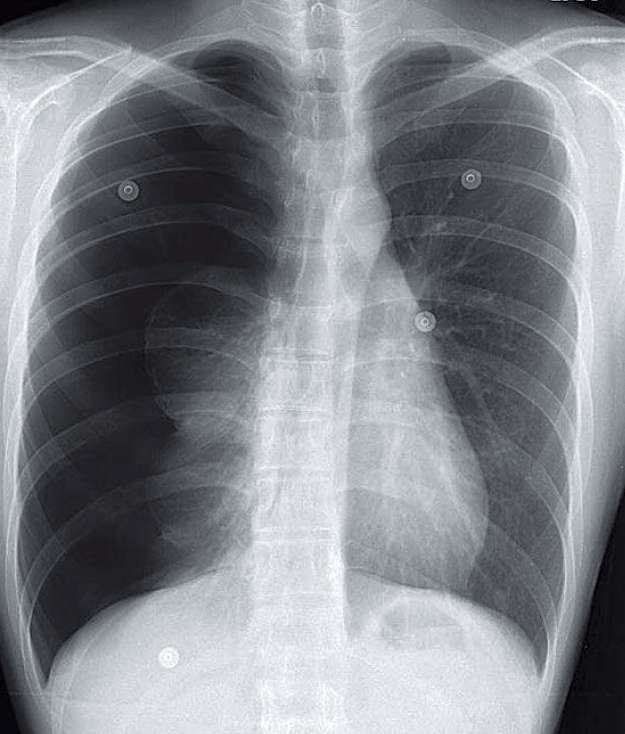

27-year-old woman with chest tightness and dyspnea Post category:Spot Diagnosis Post published:November 5, 2025 Share on Facebook Share on X (Twitter) Share on Pinterest Share on Email Share on Reddit 27-year-old woman with chest tightness and dyspnea 27-year-old woman with chest tightness and shortness of breath presents to the Emergency Department. What’s the diagnosis ? FULL CASE AND ANSWER Share on Facebook Share on X (Twitter) Share on Pinterest Share on Email Share on Reddit Read more articles Previous PostPruritic Rash in a Woman with HIV Next PostSkin Lesion in a Patient on Haemodialysis You Might Also Like Nonpruritic, Well-Circumscribed, Scale-Covered, Erythematous Plaques on Palms and Soles November 3, 2021 Unilateral Leg Swelling and Bluish Discoloration May 10, 2021 Black Discoloration of the Tongue August 12, 2021